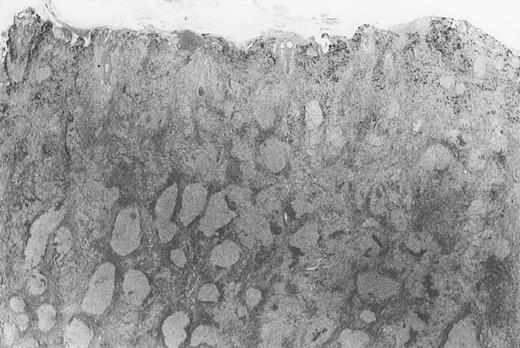

Dense infiltrate with prominent follicular pattern.

Appears within the entire dermis (patient 5).

All cases of follicular lymphoma were classified as grade 2 according to the REAL classification. Histology showed bottom-heavy lymphoid infiltrates with prominent follicular pattern (Figures3 and 4). A well-formed mantle zone around most follicles was present only in 2 patients. In the other specimens the mantle zone was either reduced (11 patients) or nearly absent (2 patients) (Figure5). A clear-cut marginal zone was never observed. Tingible body macrophages within follicles were present only in 1 patient and were absent in the other 14 patients. Cytomorphology of follicles in all patients showed variable proportions of centrocytes (cleaved follicle center cells) and centroblasts (Figure6). The interfollicular areas revealed the presence of small lymphocytes and histiocytes admixed with a few larger cells and occasionally other inflammatory cells such as eosinophils and plasma cells.